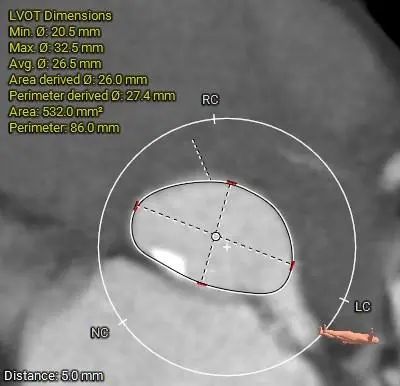

LVOT